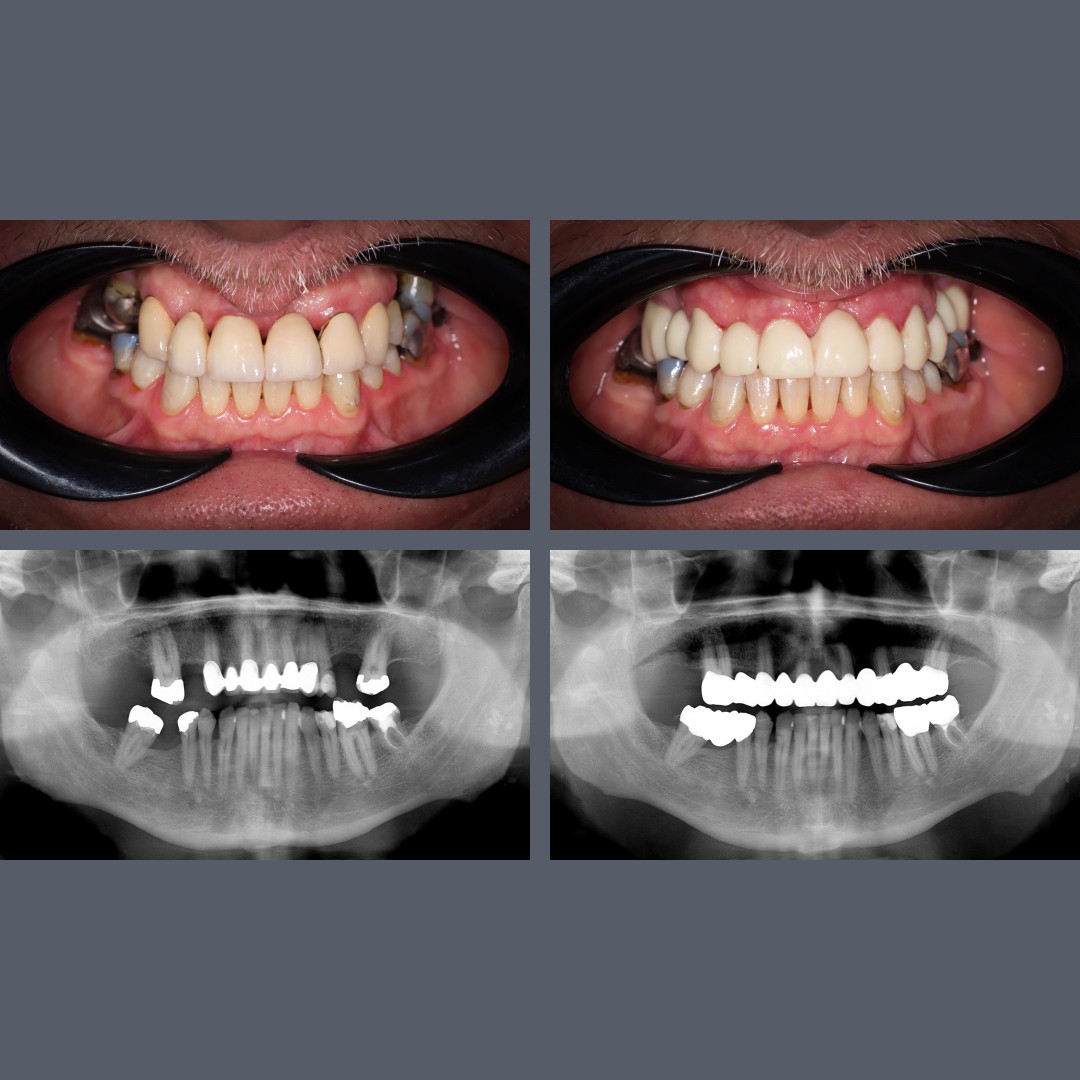

before-after

Correction of Diastema and Irregular Front Teeth with Zirconia Crowns